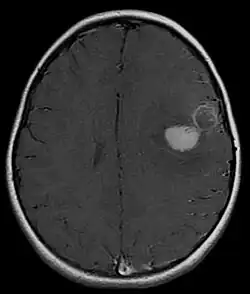

Primitive neuroectodermal tumor

Primitive neuroectodermal tumor is a malignant (cancerous) neural crest tumor.[1] It is a rare tumor, usually occurring in children and young adults under 25 years of age. The overall 5 year survival rate is about 53%.[2]

It gets its name because the majority of the cells in the tumor are derived from neuroectoderm, but have not developed and differentiated in the way a normal neuron would, and so the cells appear "primitive". PNET belongs to the Ewing family of tumors.

It is classified into two types, based on location in the body: peripheral PNET and CNS PNET.

PNET of the CNS

PNET of the CNS generally refer to supratentorial PNETs.